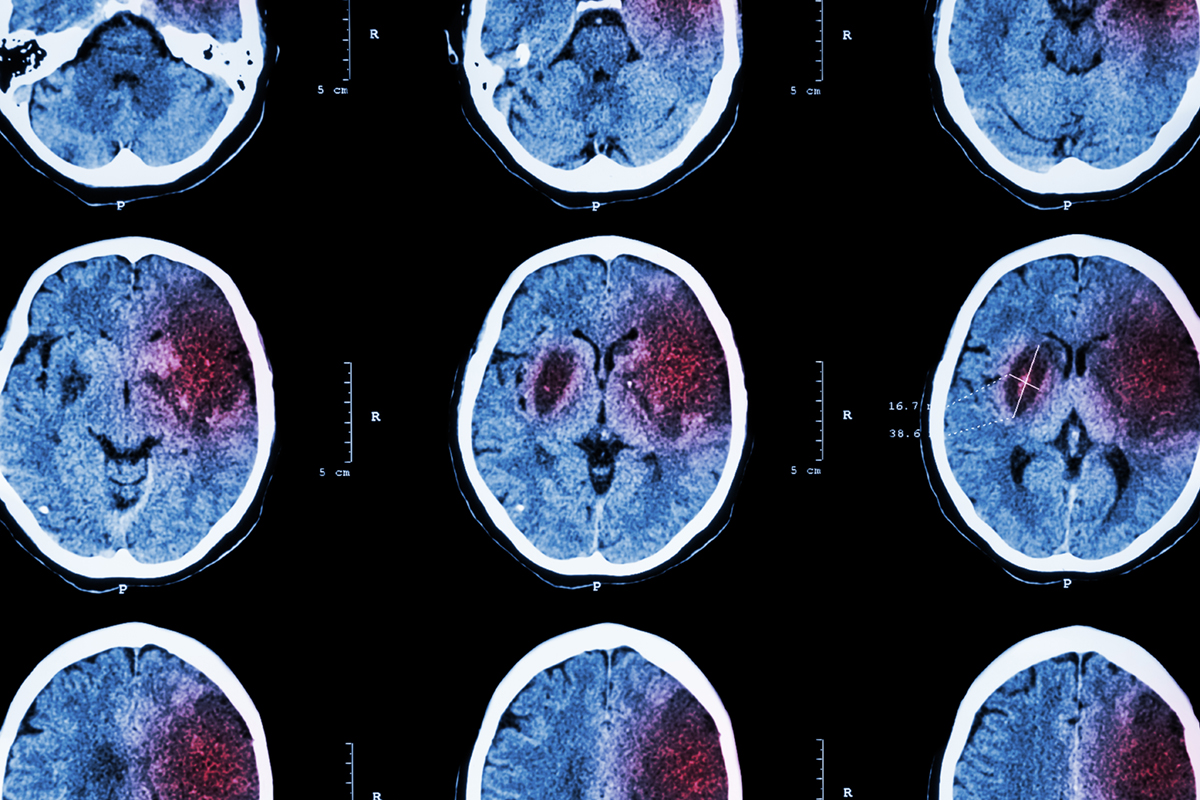

Ischemic stroke : ( CT of brain show cerebral infarction at left frontal – temporal – parietal lobe ) ( nervous system background )

脳卒中は、脳梗塞(のうこうそく)、くも膜下出血、脳出血の3つに分けられます。

脳梗塞とは、脳の動脈が詰まって血液の流れが悪くなり、脳がダメージを受ける病態です。

脳は頭蓋骨によって外力から保護されていますが、頭蓋骨の内側では、外から順番に硬膜、くも膜、軟膜の3枚の髄膜で覆われています。

くも膜と軟膜のすき間は、くも膜下腔と呼ばれていますが、ここには、脳脊髄液という脳を循環している透明な液体と、脳動脈や脳静脈が存在しています。

くも膜下出血とは、このくも膜下腔に出血を起こした状態をいいます。

そして脳出血とは、脳の血管が破れて血液が漏れ出る病態です。

昔から脳溢血(のういっけつ)という言葉がありますが、それは「血が溢(あふ)れる」という意味で、脳出血と同義です。